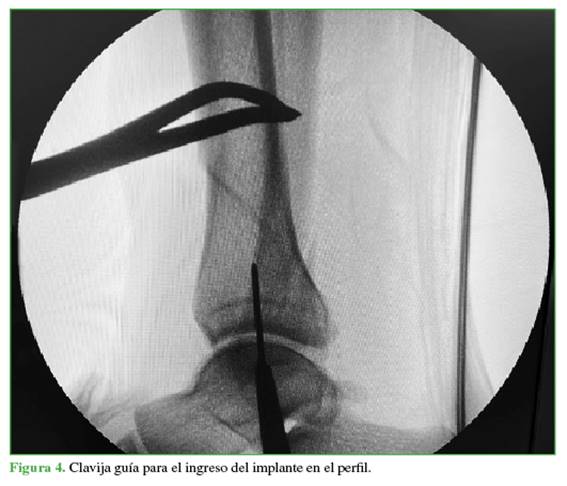

A continuación, se crea un abordaje de 3 cm desde la punta de maléolo tibial hacia distal (Figura 2). Mediante una clavija se ubica el sitio de ingreso en el centro del maléolo tibial, en ambos planos (Figuras 3 y 4), para luego agrandar con una fresa canulada la zona de ingreso (Figura 5), después se coloca una guía olivada (Figura 6) y, a través de un protector de partes blandas, se fresa el canal medular (Figura 7).